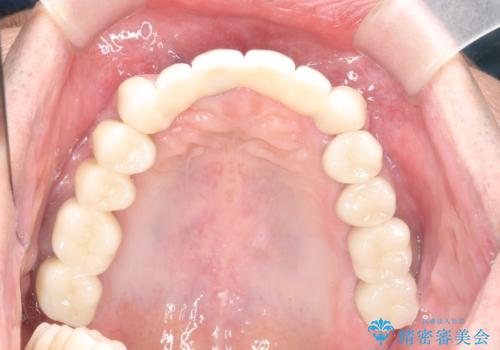

インプラント・ブリッジ補綴を含む、歯周病全顎治療

全体的な歯周病検査を行い、多数の残すことのできない抜歯の必要な歯を認めたため、残せる歯に対しての徹底的な歯周病治療、失った歯に対しブリッジ・インプラント治療を全顎的に行っていくこととしました。

長期間にわたる治療後、歯に対する意識も大きく変わりプラークコントロールも非常に良くなりました。

数ヶ月に一度のチェックをしっかりと行い、ブリッジ・インプラントが長期間使用できるようメンテンスを行っていきます。